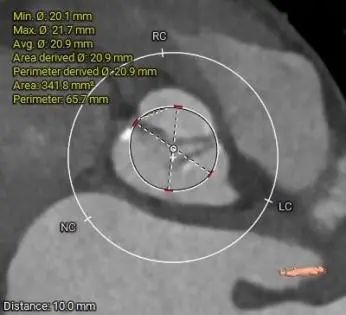

主动脉根部:

瓣环21.1mm,LVOT近直筒型

根部整体结构偏小,非横位心